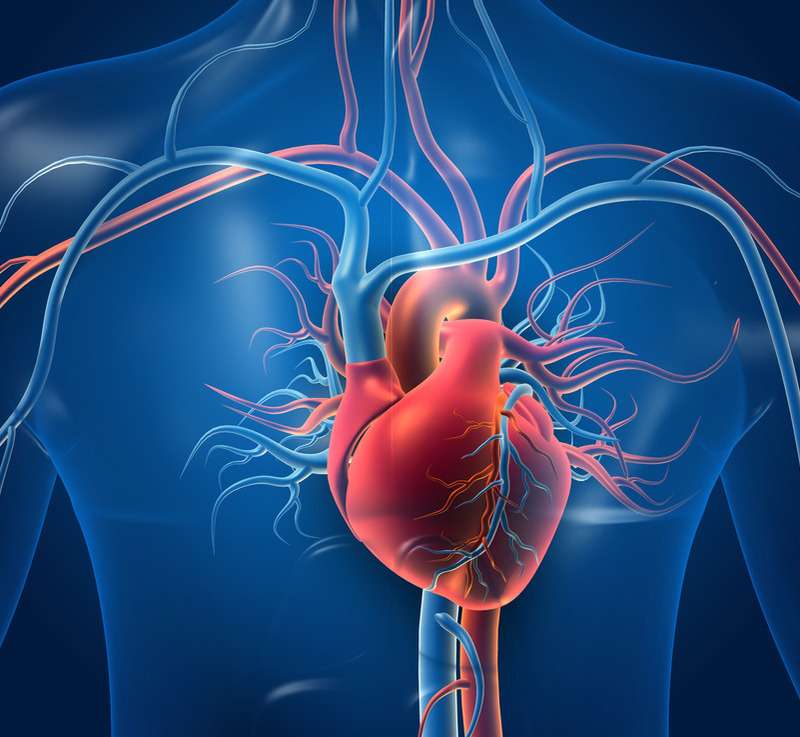

Cardiovascular Disease

Cardiology is a medical discipline that focuses on the diagnosis and treatment of cardiovascular illnesses, which affect the heart, blood vessels, and circulatory system. These ailments encompass coronary heart disease (disease of heart’s blood vessels), cardiac arrhythmias (abnormal heartbeat), congestive heart failure (heart that cannot keep up with its workload), hypertension (high blood pressure), cardiometabolic disease (spectrum of conditions that involve heart and metabolism), dyslipidemia (irregular blood lipid levels), valvular heart disease and cardiomyopathies (heart muscle diseases).